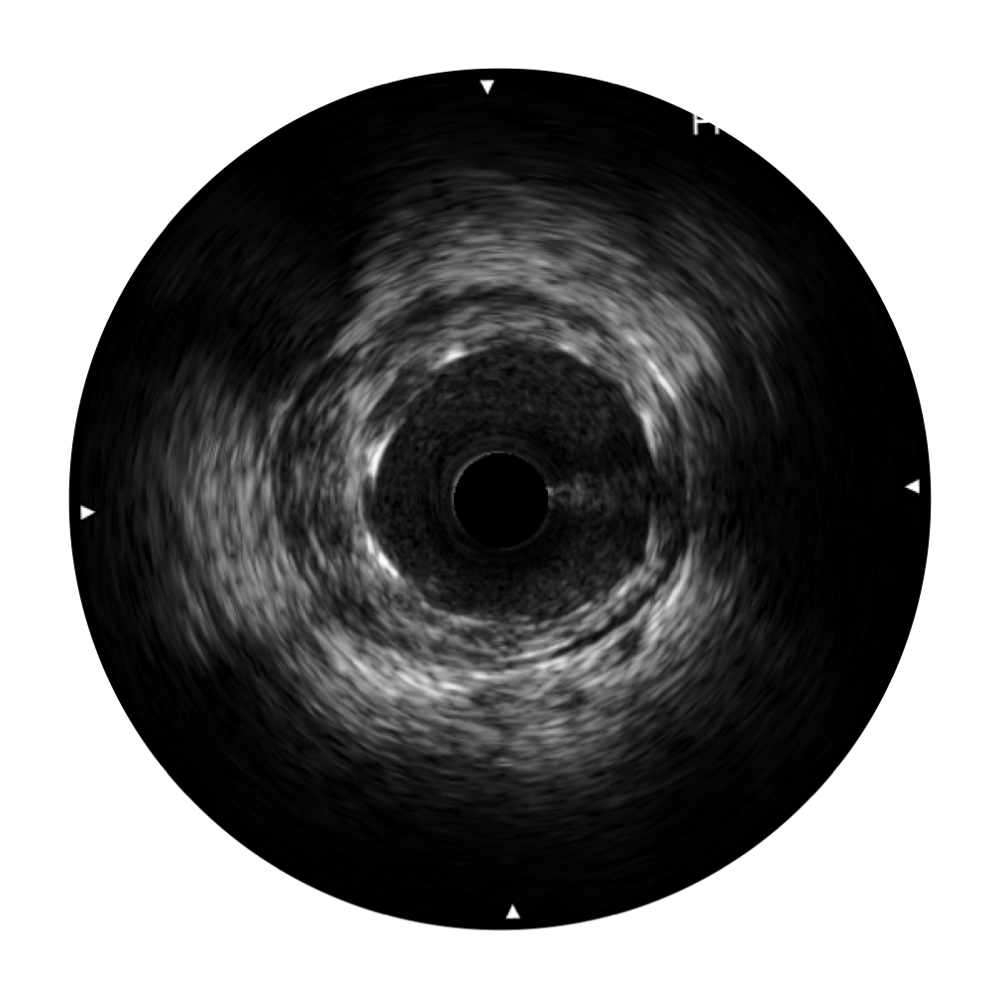

传统IVUS图像

对比传统IVUS导管成像,玖鼎集团宽频IVUS图像的近场支架梁显影更细腻,远场中膜外血管仍清晰可辨,兼顾远中近,兼顾分辨力与穿透深度